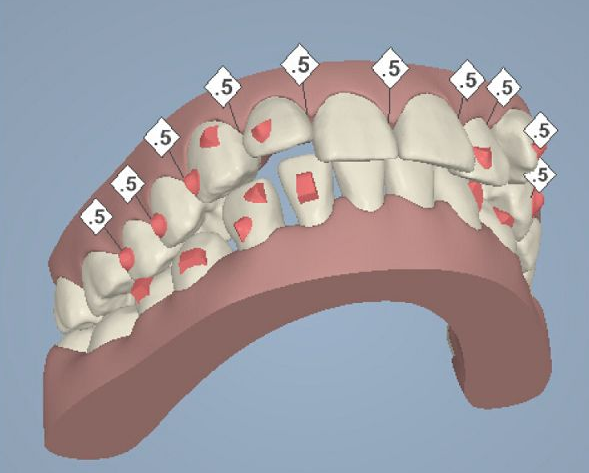

但是有了骨釘植入,就可以解決前者調(diào)節(jié)方案的煩惱,可以根據(jù)不同的調(diào)節(jié)方案,不同的調(diào)節(jié)需求,在口腔中相應(yīng)的位置植入骨釘形成口腔中的一個(gè)受力點(diǎn),同時(shí)利用正畸器,橡皮筋相互拉力的作用下,更好的幫助醫(yī)生更好的控制牙齒的移動(dòng),做到"該移動(dòng)的牙移動(dòng),不該動(dòng)的牙不動(dòng)"從達(dá)到佳的調(diào)節(jié)果。

小骨釘雖然作用很大,但是并不是所有的牙齒矯正都需要植入骨釘,只有針對(duì)復(fù)雜的正畸類(lèi)型才需要植入骨釘。

那么什么樣的牙齒情況需要植入骨釘呢?1.牙齒呈現(xiàn)深覆合或者咬合過(guò)深的患者。

2.常見(jiàn)的牙齒反頜現(xiàn)象,俗稱(chēng)兜齒或者地包天的患者

3.有牙周病、牙齒損傷嚴(yán)重沒(méi)有足夠數(shù)量的支抗牙

4.正畸前,牙縫過(guò)大,或是拔過(guò)牙,可利用植入骨釘來(lái)加強(qiáng)牙齒后退力量